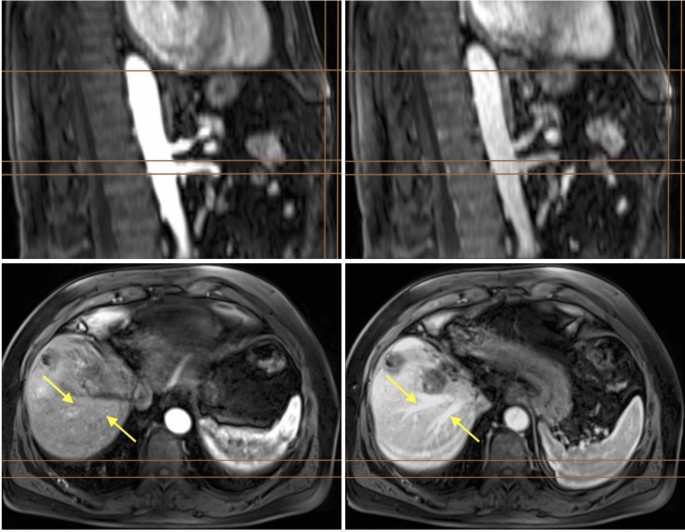

In abdominal imaging with breath-hold techniques, specific challenges arise. Not all patients can exhale uniformly across all acquisitions. Unlike brain MRIs, where anatomical structures in different phases may vary in orientation while their shape is maintained, abdominal imaging experiences significant alterations due to diaphragm movement during exhalation, affecting organ positioning relative to each other and leading to deformation. An example of this is illustrated in Fig. 1, showing the same sagittal and axial sections from both arterial and portal venous phases of the T1-VIBE sequence. The images reveal notable differences in organ positioning between phases, complicating accurate co-registration of fine vascular structures like hepatic veins due to varying exhalation levels among patients. Those characteristics made the co-registration a challenging task. Therefore, we evaluated which phase is suited best as the fixed image for this step. Co-registration quality was measured by metrics such as the Mean Squared Error, Mutual Information, Structural Similarity Index, and the Normalized Cross Correlation, as well as by visual inspection.

Arterial and portal venous phases from the T1-VIBE sequence for one subject before co-registration. The arterial phase is shown in the (left) images, and the portal venous phase in the (right). The (top row) displays the sagittal view. The (bottom row) shows the axial orientation of the same MRI. Images in the same row depict the exact same section. Due to variations in the breathing cycle, the abdominal organs do not remain in a fixed position. Brown reference lines aid visualization. Vertical lines in the top images indicate the moving abdominal border: the right line marks the border in the arterial phase, while the left line marks the border in the portal venous phase, where less air was exhaled. Horizontal lines in these images illustrate the movement of the heart (top line) and vessels (bottom lines) between phases due to breathing. Yellow arrows in the axial images point to identical spatial positions where the hepatic veins are visible in the portal venous phase. The horizontal lines indicate the borders of the liver and spleen during the arterial phase and demonstrate how they shift due to breathing.